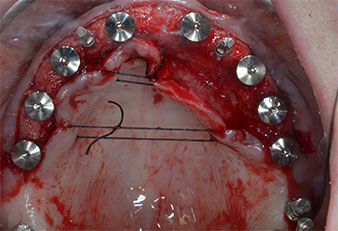

Implantatstabilität

Abb. 7: Die Implantatstabilität wird mit einem SmartPeg und dem W&H Osstell ISQ module ermittelt. Alle Werte befinden sich im mittleren bis hohen Bereich, mit einem Mindestwert von 69.